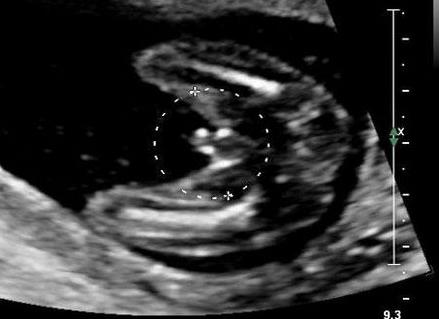

В настоящее время проще всего определить пол ребенка по УЗИ. Это самый распространенный метод. Но даже он не является достоверным, особенно на ранних этапах беременности. Обычно точный результат можно получить на сроке после 23 недель. Пол ребенка по УЗИ определяется по первичным половым признакам. У мальчиков это мошонка и половой член, у девочек большие половые губы. Но зачастую врачи ошибаются, принимая пуповину или пальцы ребенка за половой член. Яички мальчика на УЗИ могут очень напоминать большие половые губы девочки. А иногда бывает и так, что ребенок закрывается и плотно сжимает ножки, поэтому сразу определить пол ребенка по УЗИ не получается. Определение пола ребенка методом амниоцентеза, когда через прокол забирается небольшое количество околоплодной жидкости. Далее исследуется ее хромосомный состав. Проводится он на сроке 16–18 недель. Но данный способ представляет опасность для жизни малыша, потому как с иглой может проникнуть инфекция. В основном метод применяется для диагностики генетических нарушений у женщин, не прошедших первый этап скрининга. Определение пола ребенка так же возможно с помощью метода кордоцентеза. Этот метод исследования похож на предыдущий, только для исследования берется пуповинная кровь плода. Кордоцентез помогает выявить такие сцепленные с полом наследственные заболевания, как, например, гемофилию. Делают его в те же сроки, что и амниоцентез. Показания-такие же строгие. Биопсия ворсин хориона. Этот метод инвазивной диагностики позволяет выявить наследственную патологию уже на ранних сроках гестации. При помощи биопсии можно узнать пол 10-недельного эмбриона, однако, как и предыдущие методы, исследование ворсин хориона не будут назначать только для того, чтобы узнать, мальчик внутри у мамы или девочка. Гормональные исследования. Для широкого круга родителей этот анализ — дело недалекого будущего. Пару лет назад израильские врачи научились устанавливать пол младенца уже через две недели после зачатия — по содержанию гормона хорионического гонадотропина человека (ХГЧ) в крови будущей мамы. Дело в том, что у женщин, вынашивающих девочек, уровень ХГЧ оказался в среднем на 18,5% выше, чем у тех, кто вынашивает мальчика. Пока подобный анализ на ХГЧ используется в основном для диагностики беременности. Подробнее ...